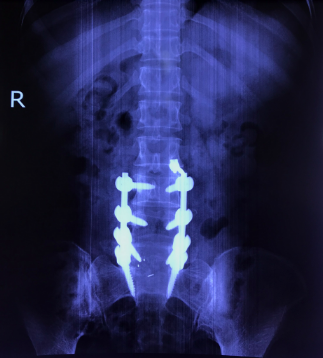

Hình ảnh: Hình ảnh 3D phẫu thuật TLIF

Cho tới nay, phương pháp phẫu thuật nắn chỉnh trượt, cố định cột sống bằng nẹp vít qua cuống, ghép xương liên thân đốt lối sau (sử dung Cage) được cho là hiệu quả nhất, áp dụng phổ biến nhất để điều trị trượt đốt sống thắt lưng.